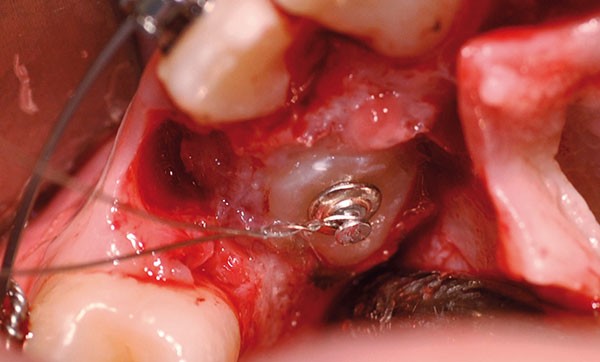

chirurgie à visée orthodontique : extractions de dents de sagesse, dégagement de dents incluses, poses de mini-vis et mini-plaques…